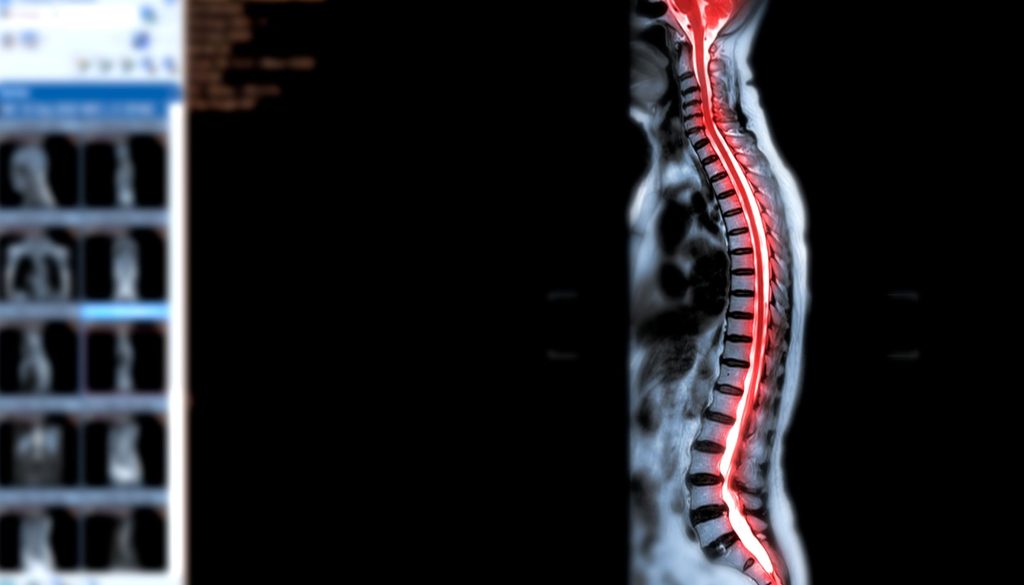

جراحة النخاع الشوكي تعتبر من العمليات الجراحية الحساسة والمعقدة، وتحتاج إلى تخطيط دقيق واستعداد نفسي وجسدي. يُعتبر النخاع الشوكي الجزء الأساسي من الجهاز العصبي المركزي، ويمتد من الدماغ عبر العمود الفقري. أي تدخل جراحي في هذه المنطقة يتطلب عناية فائقة وفهماً دقيقاً لمخاطر الفوائد المحتملة. في هذه المقالة، سنقدم نصائح وتعليمات للمرضى الذين يخططون للخضوع لجراحة النخاع الشوكي.

تُجرى جراحة النخاع الشوكي لعلاج مجموعة متنوعة من الحالات مثل الإصابات، الانزلاق الغضروفي، الأورام أو الأمراض التنكسية. تهدف هذه الجراحة إلى تخفيف الألم، استعادة الوظيفة، أو منع التلف الدائم.

– الفحوصات المخبرية والاختبارات التصويرية مثل الأشعة، الرنين المغناطيسي، أو الأشعة المقطعية تساعد في تحديد الاستراتيجية المثلى للعلاج.